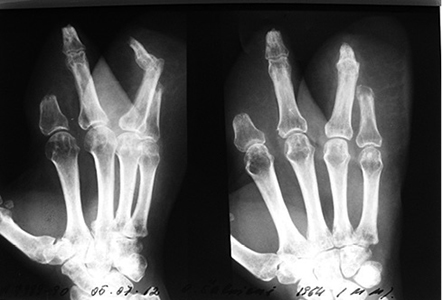

1 pav.

2 pav.

Kairės plaštakos minkštųjų audinių Degloving amputacija. Nugarinis ir delninis paviršiai (1 ir 2 pav.)